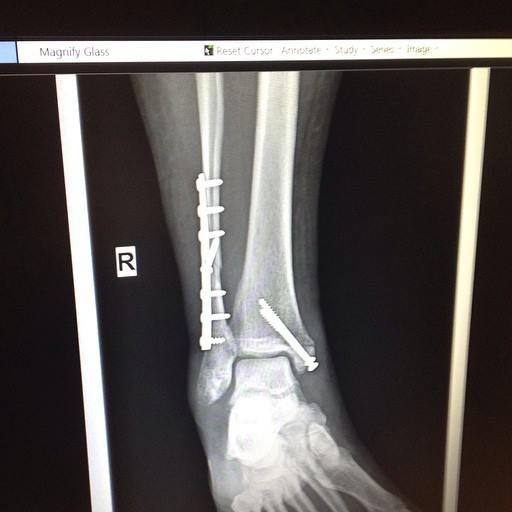

I was scared, disappointed, and really angry. I had transformed from this fiery ball of passion and energy to this crumpled mass surrounded by scared sad faces in a near ominous silence. I knew there would be surgery and then recovery and after that rehab to get through, just to be able to walk normally again, let alone skate. At that moment it felt as though all of that momentum, all of that hard work I’d put in, was all for nought. That maybe I wasn’t meant to be out there like I thought I was, maybe this was all I was able to do when it came to my derby career, that this was it, no more skating.

I’ve been back skating now for as long as I’d been out and I can honestly say I feel more confident, more sure of myself, and better than I was before my ankle break. Big Injury doesn’t have to be the end. There are plenty of people in my life who think I’m crazy for going back to a sport that landed me in an operating room with a bunch of metal in my leg, and the possibility of more to come. I am still scared sometimes. I think “what if…” each time I lace up my skates and head out onto the track. But that’s the thing about derby; once you fall in love with it, you never want to leave it. It’s a part of who you are. I even got myself a little reminder shortly after I started skating again, a tattoo of a robot derby girl on the inside of of my ankle between the scars of where my new metal pieces now reside (her name is Rhonda Swantron and I love her).